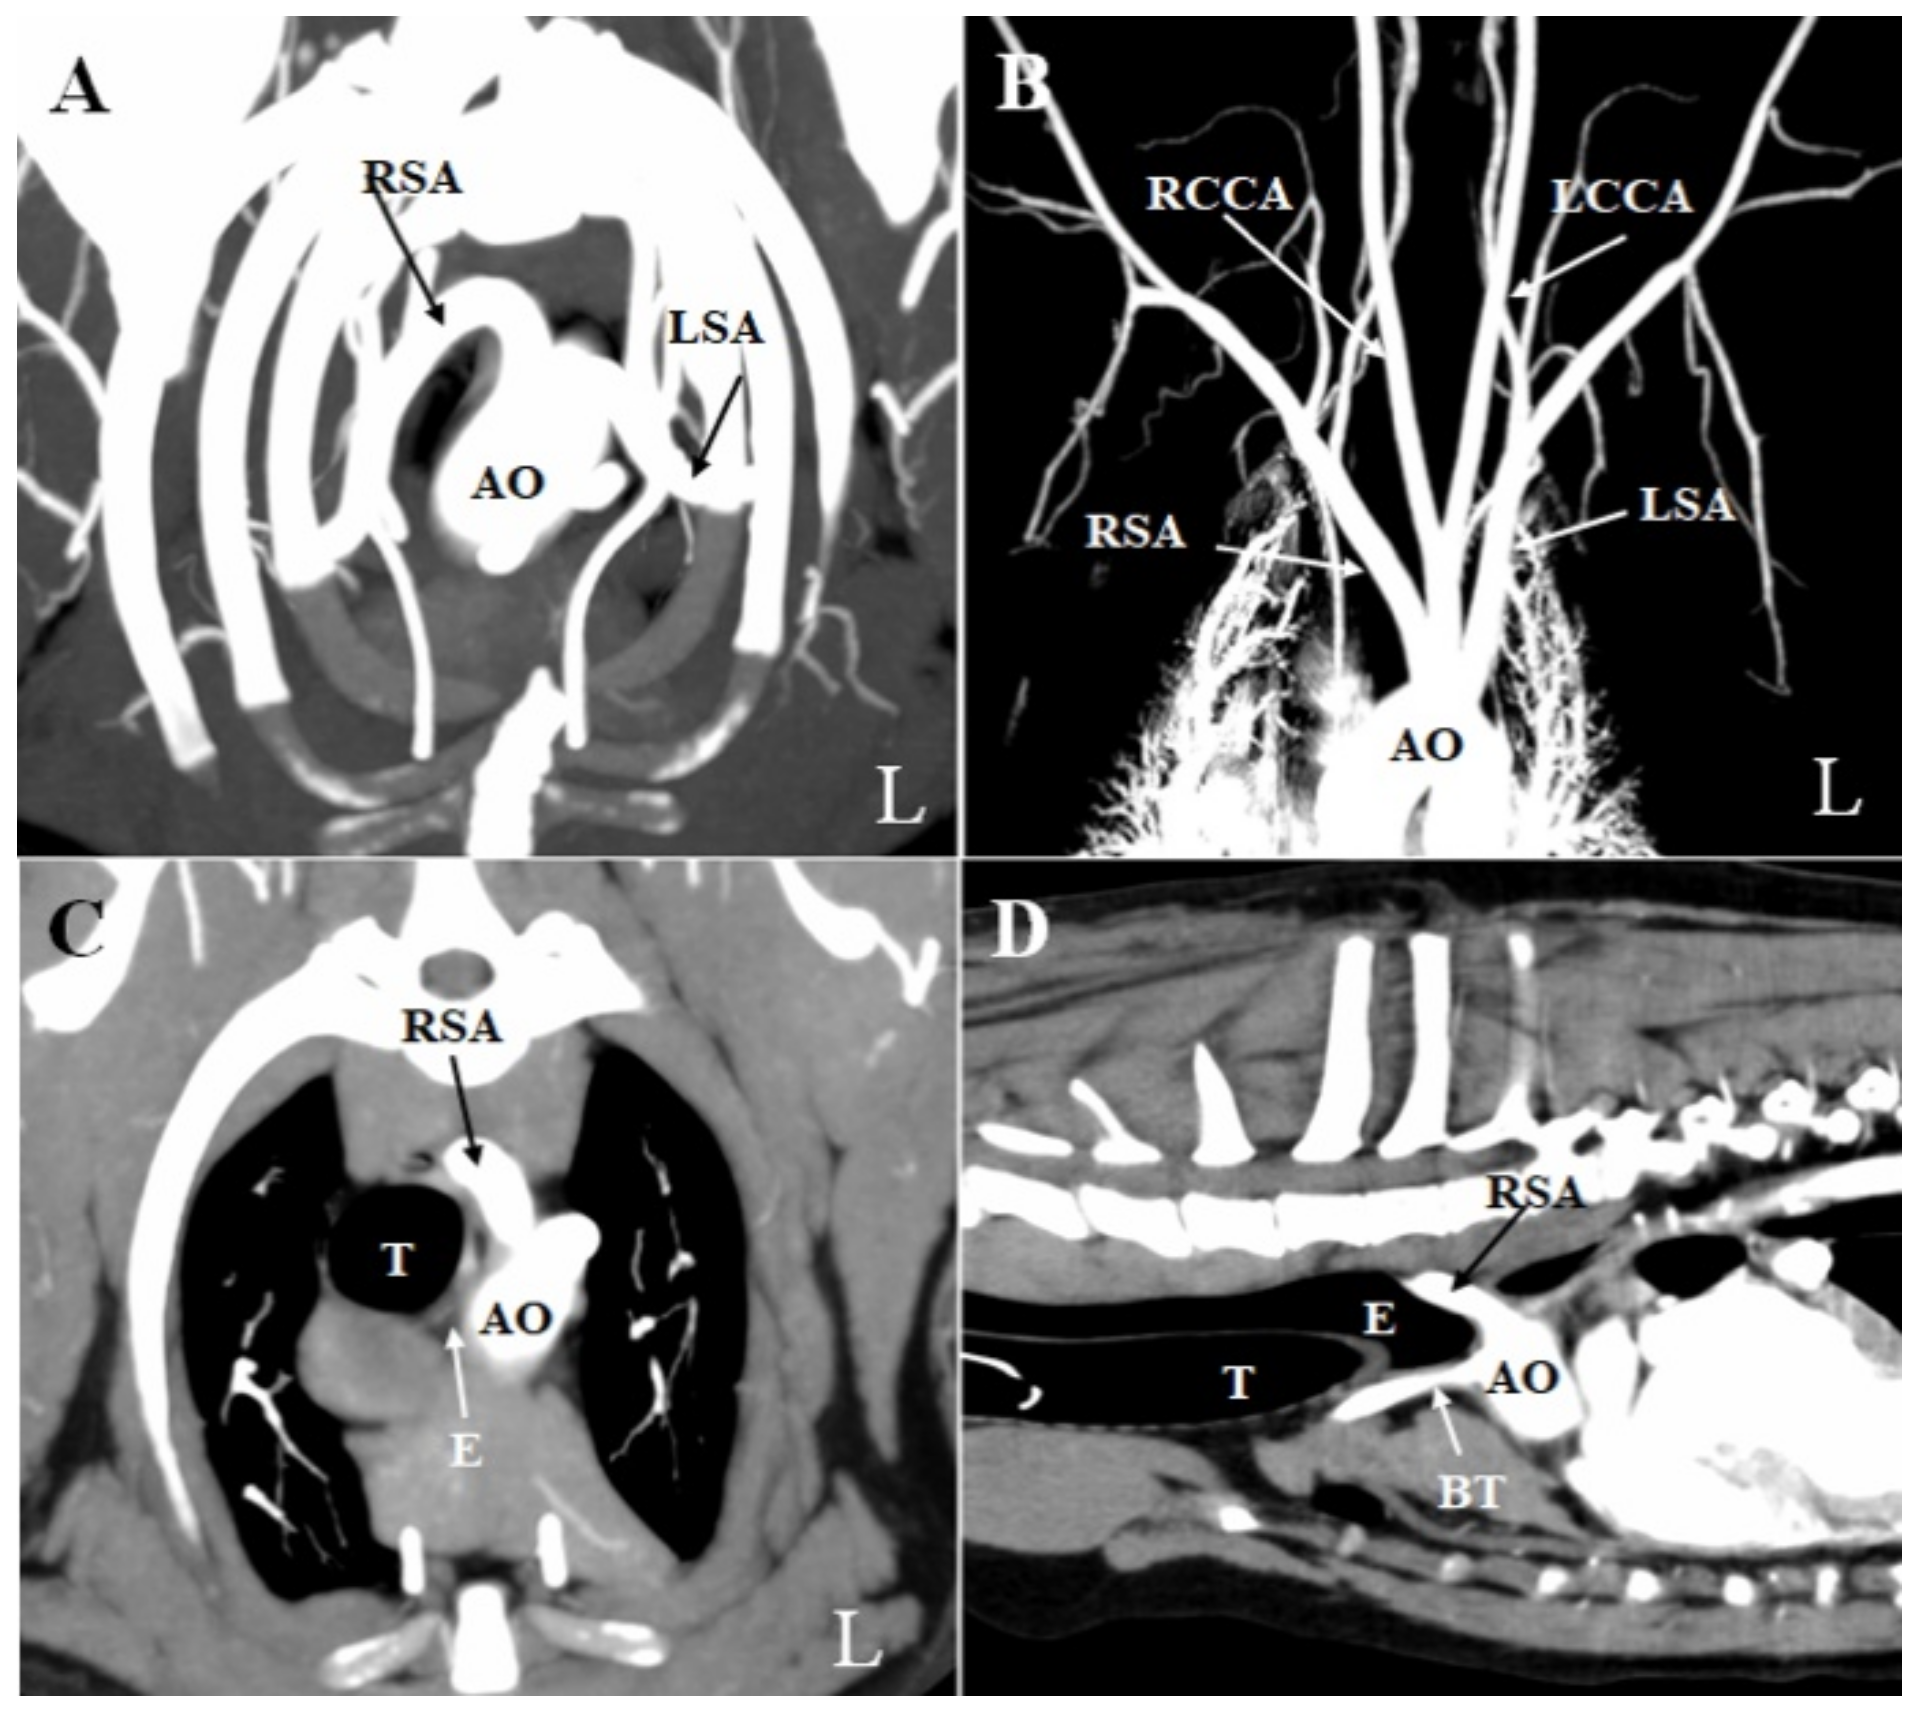

2. Case Presentation